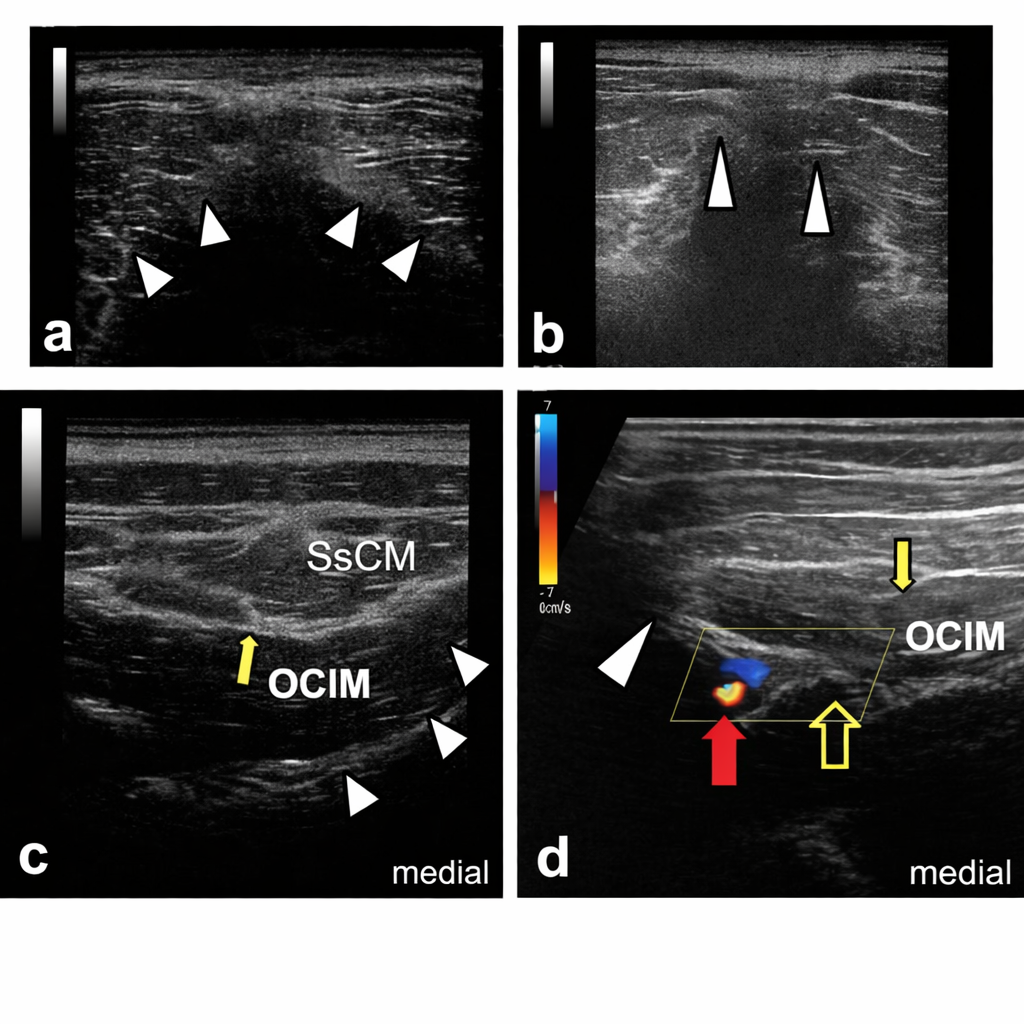

Occipital Nerve Blocks

- Ultrasound-guided injection around irritated occipital nerves

- Highly effective for occipital neuralgia and cervicogenic headaches